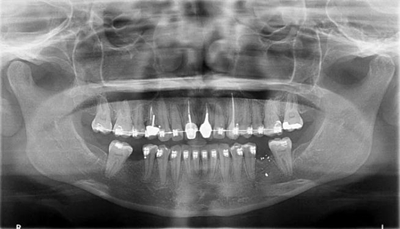

圖1a.病例1在正畸排齊后的臨床和放射學檢查。曲面斷層片顯示初期治療后良好的牙根排列,但下頜右側(cè)第二磨牙仍舊有些近中傾斜

圖1b.臨床檢查顯示牙槽嵴萎縮,右下第一磨牙的無牙間隙近遠中距離為6.5mm,左下第一磨牙為9mm

一位29歲的女性患者,雙側(cè)下頜第一磨牙缺失,來院要求修復治療。缺失牙從未進行修復,導致牙槽嵴萎縮,第二磨牙近中傾斜,第三磨牙已拔除。其咬合關(guān)系為尖牙關(guān)系安氏II類錯畸形,作者團隊決定通過正畸治療來糾正錯畸形和改進咬合關(guān)系。因此,其治療計劃包括雙側(cè)下頜第二磨牙直立和種植體支持式修復體來替代缺失的第一磨牙。

為患者采用了直絲弓自鎖托槽(Damon,Ormco)。最開始用0.016×0.025 英寸的不銹鋼弓絲(Damon,Ormco)進行矯正和排齊,歷時7 個月。在磨牙直立加力之前,下頜第一磨牙位點無牙區(qū)的近遠中距離為右側(cè)6.5mm、左側(cè)9mm(圖1)。磨牙遠移和直立的目標是實現(xiàn)雙側(cè)最終冠修復體的近遠中直徑達到10mm。右側(cè)第一磨牙位點的大小差異比左側(cè)更大,牙槽嵴吸收更多,頰舌徑約4.5mm(圖2)。在詳細解釋同期牙槽嵴增量和加速磨牙直立程序后,患者選擇右側(cè)位點進行種植治療。因此,為了加速該位點的空間建立,圍繞第二磨牙行選擇性去皮質(zhì)術(shù)和同期牙槽嵴增量術(shù)。